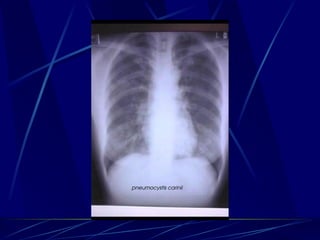

Pneumocystis carinii Parasito extracelular Quistes en tejidos teñidos por plata 1er causa de RIP en SIDA

Pneumocystis carinii Enfermedad: Neumonía Se juntan con neumocitos tipo I y los matan Apariencia de Panal de abeja en H&E Rayos X: infiltrato parchoso (vidrio espulido) Diagnóstico:  Tinción de plata Tratamiento: TMP/SMX

Pneumocystis carinii Parasitoextracelular Quistes en tejidos teñidos por plata 1er causa de RIP en SIDA

Pneumocystis carinii Enfermedad:Neumonía Se juntan con neumocitos tipo I y los matan Apariencia de Panal de abeja en H&E Rayos X: infiltrato parchoso (vidrio espulido) Diagnóstico: Tinción de plata Tratamiento: TMP/SMX